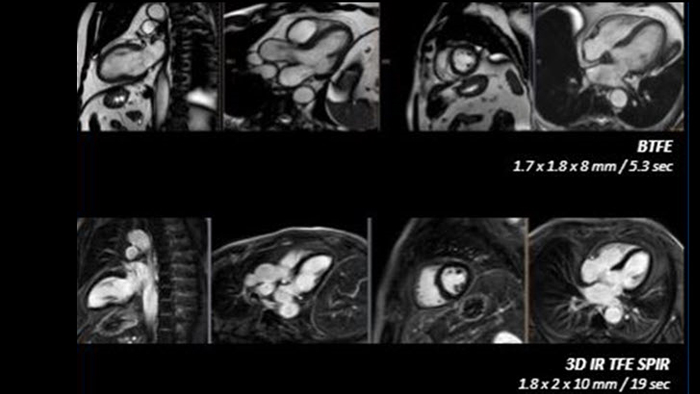

Realize the potential of MR throughout the pathway with ultrafast exams, optimized workflow, high-quality diagnostic imaging and enhanced patient comfort.